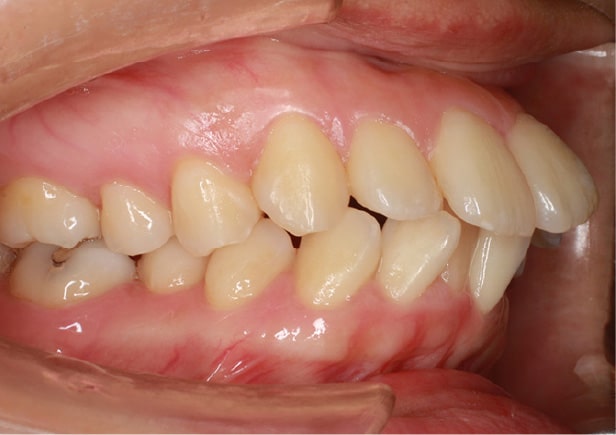

矯正after

矯正種類 ワイヤー矯正

症例 上下額叢生

治療期間 2021年12月〜2024年10月

性別/年代 男 13歳

治療費 748,000円

コメント

適切な時期に治療が開始できたので、歯並びだけでなく顎や顔貌も理想的に成長しました。歯磨きもしっかりできるようになりました。